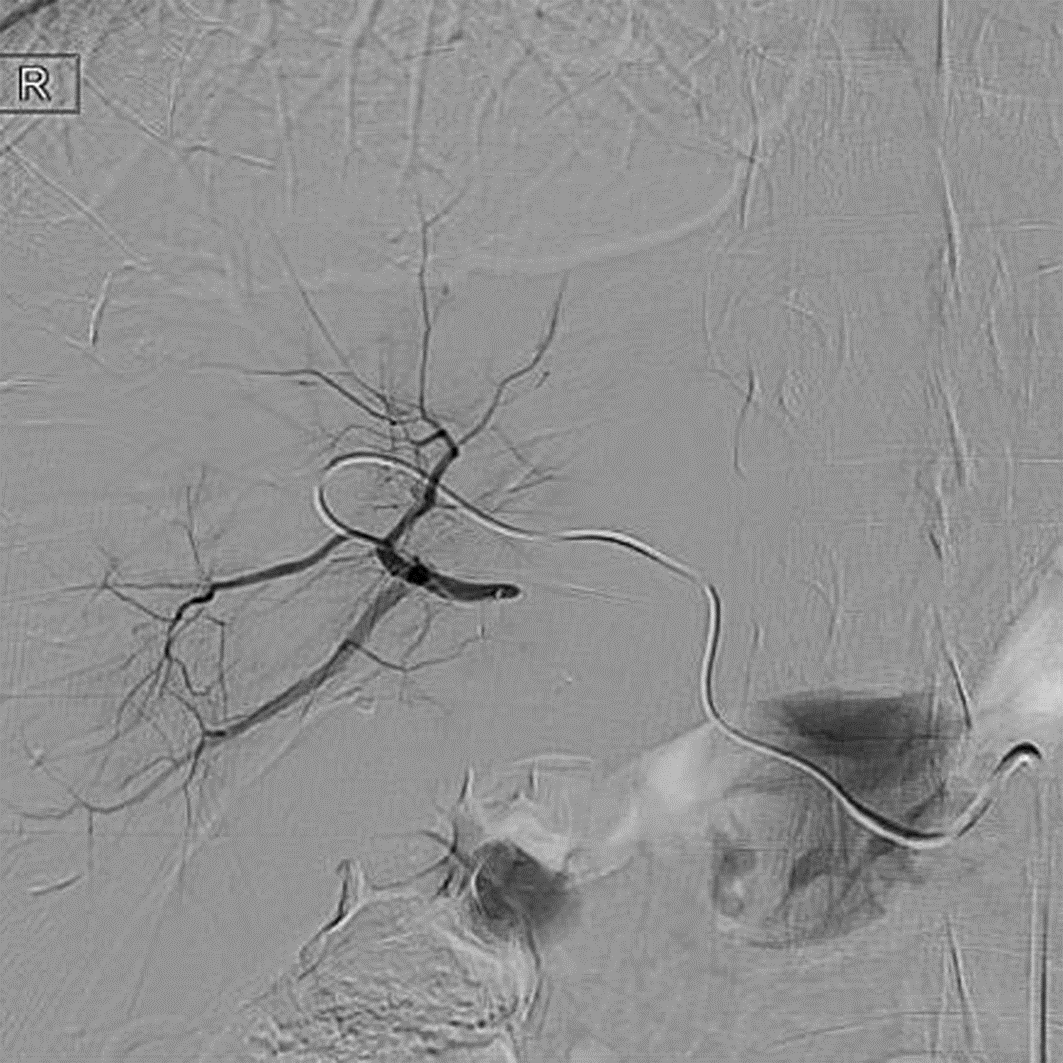

Diagnosis and treatment of hepatic pseudoaneurysm with bile leakage and bile duct hemorrhage after transplantation of donor liver with right hepatic artery variation: A case report

Tian HAN, Rui ZHANG, Zhiyong SHI, Li ZHANG, Jun XU

2022, 38(12): 2818-2820. DOI: 10.3969/j.issn.1001-5256.2022.12.024

Abstract(1727) HTML (1056) PDF (2268KB)(55)